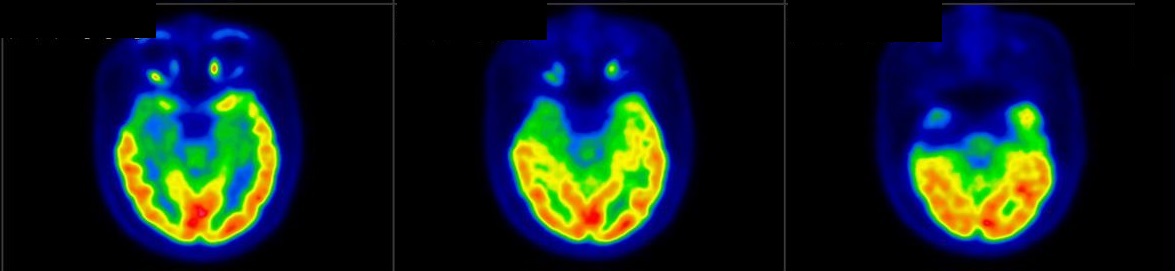

Neurological Diseases

- Dementia

PET/CT scans with special tracers can show 3-dimensional images of blood flow and biomolecules deposition in the brain for diagnosis and monitoring the therapy progress of various neurological diseases, such as Alzheimer's, Dementia, Parkinson's disease, Huntingdon's chorea and autism. In 2018, the National Institute on Aging-Alzheimer's Association (NIA-AA) had revised the definition of Alzheimer's Disease (AD) from a syndrome diagnosed by a set of clinical criteria to a biological construct using abnormal protein deposits to define AD as a unique neurodegenerative disease that can lead to dementia. Our hospital has almost 20 years of experience in producing specific tracer to detect abnormal protein deposition in the brain.

- Epilepsy

For some types of epilepsy patients, PET/CT scans can localize the epilepsy-causing focus in the brain. Modern stereotaxic neurosurgery can then cure epilepsy permanently by excising the focus.